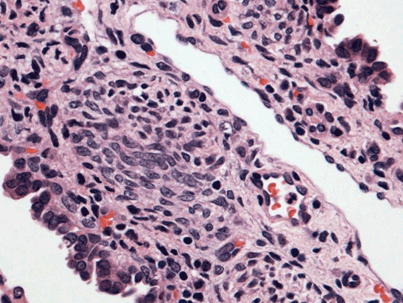

The following is a chest X-ray and CT-scan slide, showing the nice reexpansion of the left lung after few months of the surgery.

![]() Figure 14 |